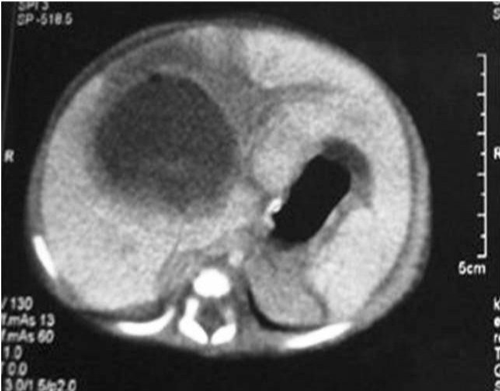

A premature newborn girl born at 33 weeks of gestation, weighing 2250 g was admitted to neonatal intensive care unit (NICU) with hydrops fetalis. Umbilical catheterization was done for IV access and for TPN. Nine days later, baby developed thrombocytopenia, leucocytosis, and abdominal distension. Blood and urine cultures were obtained, but no pathogen was detected. The umbilical catheter was withdrawn as it was thought to be a possible site of infection. Two days after catheter withdrawal, her clinical condition deteriorated. She was dehydrated and had abdominal distention, abdominal tenderness, and hepatomegaly. Bedside abdominal US revealed two compound cystic cavities, measuring 32×18 mm and 11×5 mm. US could not distinguish if these lesions were due to liver abscess, hematoma, or cavernous hemangioma. Laboratory analysis revealed WBC 13.8 103/µL, Hb 9.5 g/dL, PLT 32x103/µL, SGPT 79 U/L, SGOT 230 U/L, LDH 556 IU/L, and CRP 9.46 mg/L. Hemodynamic resuscitation were initiated. Repeat US the next day revealed a single, large, cystic cavity measuring 45×35 mm. Abdominal CT with intravenous contrast confirmed the diagnosis of liver abscess (Fig. 1). Vancomycin (15 mg/kg q6h IV) and meropenem (20 mg/kg q8h IV) were continued. After correction of her anemia, thrombocytopenia, and fluid and electrolyte disturbances, she underwent open surgical drainage of the abscess with lavage of the abscess cavity with warm saline and drainage with a suction drain. Culture of the pus from the abscess was negative. Postoperative recovery was uneventful, drain was removed on 5th postoperative day and baby was discharged on the 18th postoperative day. Regular follow-ups did not show any recurrence with normal ultrasound of liver US at 18 months.

Figure 1: Abdominal CT with intravenous contrast revealed a single, large, cystic cavity measuring 45×35 mm. confirmed the diagnosis of liver abscess. |